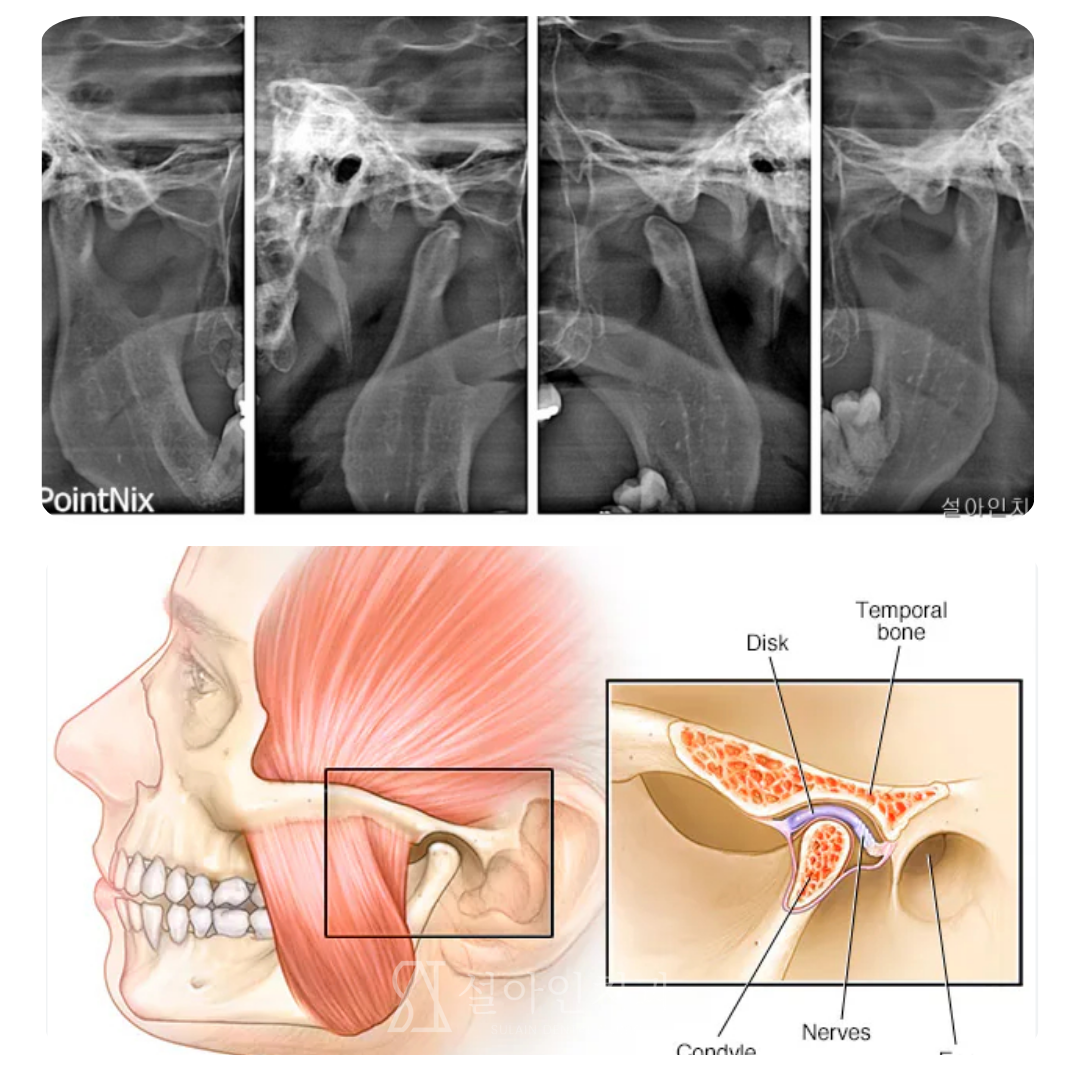

턱관절 통증, PDRN 주사로 치료하는 프롤로 주사요법